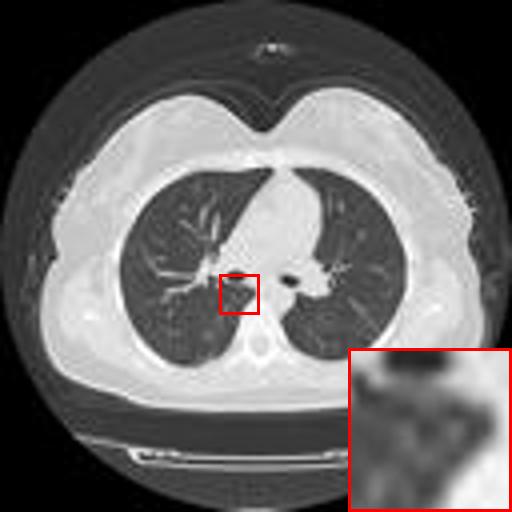

Refer to caption

(a) Original HD image

(b) Bicubic

(c) EDSR

(d) WDSR

(e) T-GAN

Figure 4: Reconstruction results of each algorithm for abdominal MRI images.

The PNSR/SSIM test results for the knee MRI test images for all contrast methods are shown in Table 1. The PNSR/SSIM test results for the abdominal MRI images are shown in Table 2. It’s worth noting that all metrics were calculated on cropped photos in order to eliminate the impact of non-subject areas. The quantitative results show that for knee MRI images, our proposed TT\mathrm{T}-GAN model achieves the best performance on the PSNR/SSIM metrics. For abdominal MRI images, our model essentially achieves optimal performance, with individual image WDSR slightly outperforming our model. The experimental results cousin that our model is more suitable for medical image super-resolution reconstruction than the existing deep learning-based image super-segmentation models.

We likewise give the visualization comparison results for each comparison algorithm, as shown in Fig. 3 and Fig. 4. It can be seen that the reconstructed images based on bicubic interpolation and deep learning based EDSR and WDSR both show oversmoothing phenomenon and some loss of detail information of the images. In contrast, our T-GAN performs better for the reconstruction of detail information due to the texture Transformer structure.